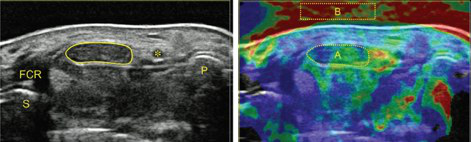

Ultrasound

Hannes Gruber, Alexander Loizides

- Sonographic evaluation of soft tissue masses (incl. MSK contrast-enhanced sonography (CEUS))

- Sonography of the musculoskeletal system

- Sonographic assessment of functional musculoskeletal disorders

The surgical ultrasound section is a leader in the development of ultrasound techniques for the evaluation of peripheral nerves, ultrasound-guided nerve root infiltration and pain therapy. One of the most recent publications illustrates our work.

- Sonography of carpal tunnel: definition of cut-off values

- Sonoelastography of epicondylitis, plantar fasciitis and Achilles tendon: accuracy in comparison with histology

- Sonographically guided (SG) injections in CTS: sonoelastographic appearance

- MR tractography (DTI, ADI) in median nerves of healthy volunteers and CTS patients: comparison with sonography.